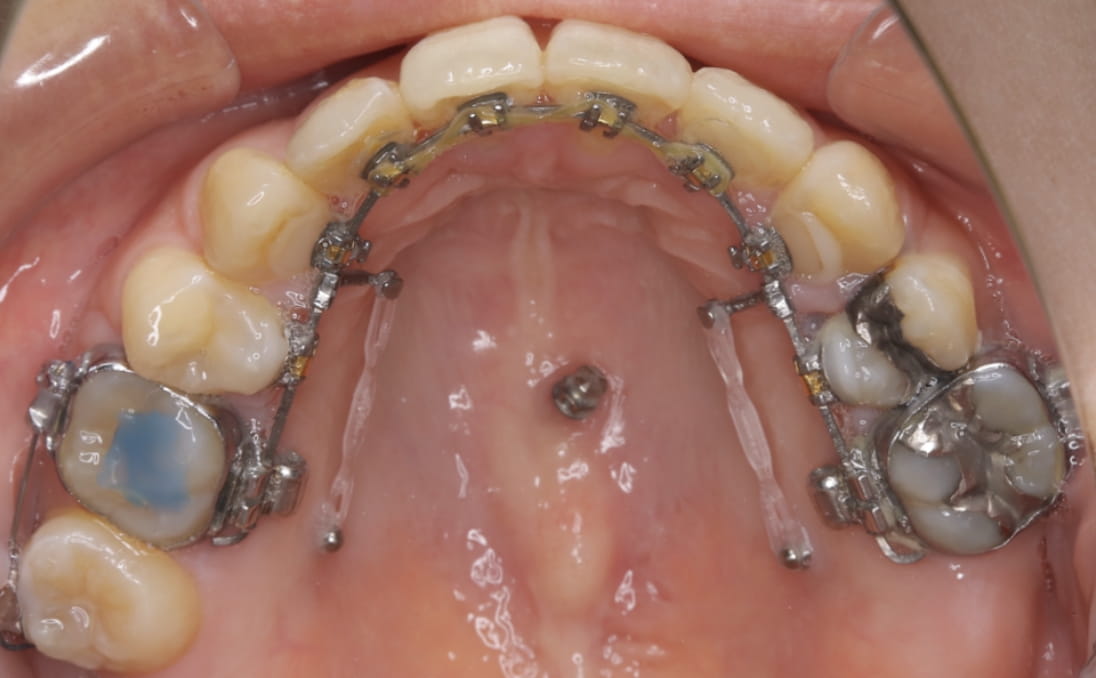

《歯槽性上下顎前突を伴う叢生》

症例42

性別:女性 年齢:13歳 お住まいの地域:奈良市

主訴 上の2本が出てるのが気になる

治療装置 上裏側、下表側からのハーフリンガル矯正装置

抜歯 上下4本

治療期間 2年8ヶ月

診断名 歯槽性上下顎前突を伴う叢生

副作用 歯肉退縮・歯根吸収・歯髄壊死・癒着による予期せぬ歯の動き

より綺麗にする希望を達成するために上下4本を抜歯。前歯のリトラクション(後方移動)を行うためにインプラントを使用。若年層ではあるが、インプラントの安定がよく、ヘッドギアに切り替えることなく、順調に進められた。

治療中(19ヶ月後)